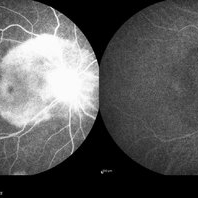

Occlusive Vasculitis Occlusive VasculitisJan 28 2023 by Anjana Mirajkar, MS Ophthalmology Wide field FA image of RE of a 40 year old female a case of occlusive retinal vasculitis. Photographer: Dr. Anjana Mirajkar -Retina Foundation, Ahmedabad Condition/keywords: occlusive retinal vasculitis